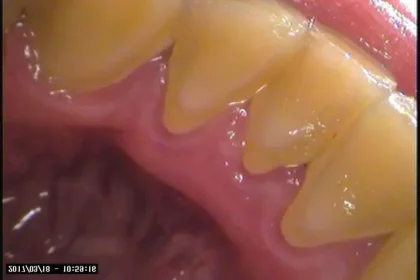

こちらの2枚のお写真は前歯の下の舌側の部分です。

歯石をこのまま放置しておくと、歯茎がパンパンに腫れ出血し、虫歯や歯周病、口臭などを引き起こします。